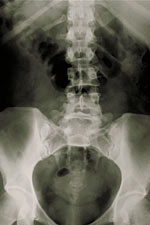

Radiografías de la columna vertebral, del cuello o de la espalda

Pueden hacerse radiografías de la columna vertebral para observar sus distintas zonas. Llamamos a estas zonas secciones cervical, torácica, lumbar, sacra y coccígea. Para diagnosticar problemas en la columna vertebral, la espalda o el cuello, también pueden realizarse otras pruebas. Estas pruebas son las siguientes: mielografía, tomografía computarizada, resonancia magnética y gammagrafía ósea.